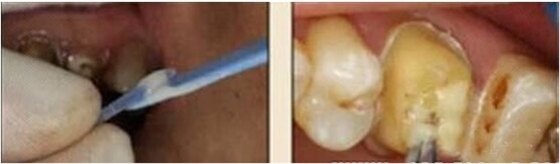

使用全酸蝕粘結(jié)系統(tǒng)粘接纖維樁時(shí),需要應(yīng)用磷酸凝膠對(duì)根管進(jìn)行酸蝕處理,然后再?gòu)氐讻_洗干凈。根管內(nèi)酸蝕劑的殘留是臨床上經(jīng)常發(fā)生且容易被忽視的問題,也是影響纖維樁粘接的重要因素之一。單獨(dú)使用三用槍即使反復(fù)沖洗也很難將根管內(nèi)的酸蝕劑清除干凈,尤其是后牙根管。臨床建議應(yīng)用注射器、三用槍和柱狀毛刷,三者聯(lián)合使用反復(fù)沖洗,以免酸蝕劑殘留于根管內(nèi)(圖 19-1至圖 19-4)。有條件者也可使用超聲波蕩洗根管。

圖19-1:冠部及根管全酸蝕。圖19-2:三用槍沖洗。圖19-3:注射器沖洗。 圖19-4:根管毛刷清洗。